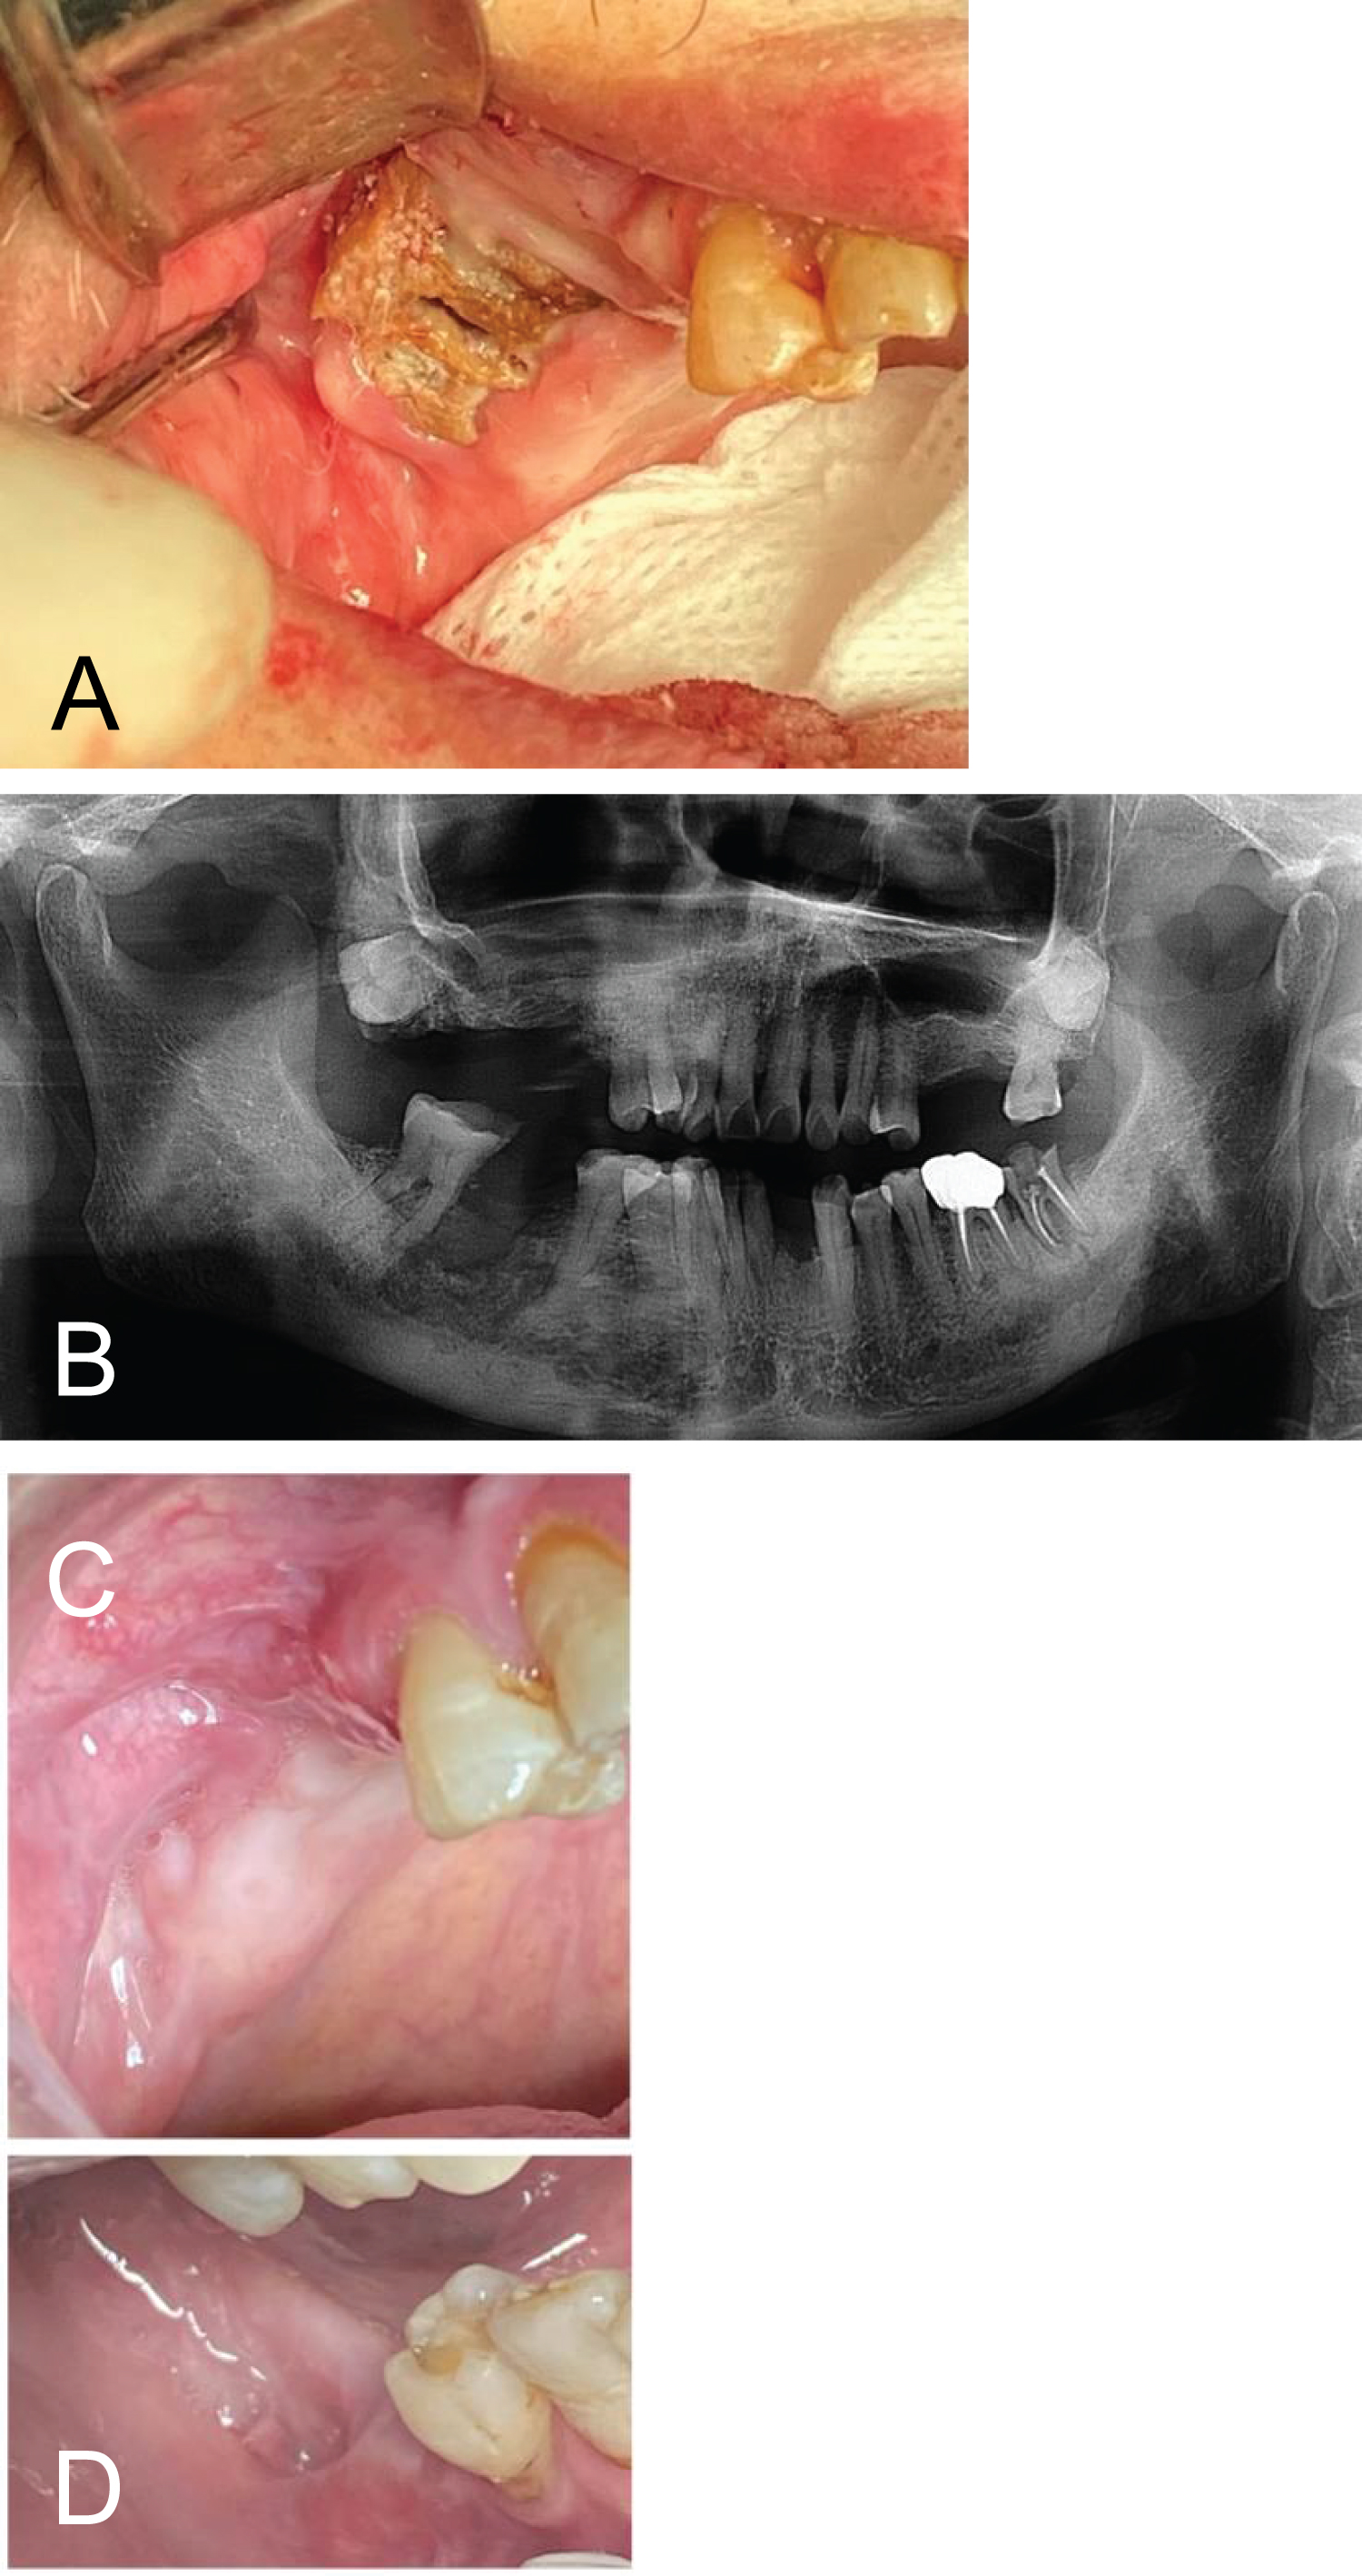

This was an 83-year-old male who had stage IV multiple myeloma. He had been treated with chemotherapy and 10 infusions of zoledronate (Zometa) three years prior to referral. He was referred by his general dentist for infection of the right mandible. Examination showed necrotic bone in the right maxilla and an intraoral fistula with purulent discharge in the right mandible (Figure 1a). He also had purulent discharge from the gingival sulcus around every tooth. Panoramic radiograph showed a radiolucency in the right maxilla and mandible (Figure 1b). The patient had been treated conservatively for three years with chlorhexidine mouthwash and oral amoxicillin. During this time the infection was under control. However, the necrotic bone in the right maxilla remained unhealed and the right mandibular lesion continued to discharge. He then developed Clostridium Difficile colitis and the amoxicillin was discontinued following which the infection quickly recurred. At this time, his cancer also relapsed, and his general health deteriorated. His chemotherapy was repeated and when his health was improved, surgical debridement and long-term IV antibiotics were proposed. Due to a low hemoglobin (9 mg/dL) and low platelet count (60k), the patient received two units of packed red blood cell, as an outpatient, prior to debridement. A peripherally inserted central catheter (PICC) line was placed prior to the surgery and monitored anesthesia care was managed by a separate anesthesiologist in the private practitioner's freestanding office. Microbiology specimens were collected and sent to Quest Diagnostics Laboratories. Two teeth were removed and sequestrectomy was performed on the mandible. Following this, sequestrectomy was performed on the right maxilla where an oroantral defect was closed with a buccal fat pad and a buccal mucosa flap. Specimens were sent for pathological examination. Intravenous ertapenem was commenced immediately after the surgery as an empiric antibiotic following outpatient consultation with an infectious disease specialist. He was maintained with nil by mouth for two weeks postoperatively and was given total parenteral nutrition at home following consultation with appropriate specialists. Microbiology reported normal oral flora sensitive to most antibiotics. Ceftriaxone was added to the ertapenem one week postoperatively. After a six-week intravenous antibiotic course, he was given three further weeks on oral penicillin VK. The patient is currently doing well with no exposed bone, and infection free for almost one year following completion of treatment (Figure 1c and Figure 1d).

Figure 1: (a) Necrotic bone exposure in right maxilla after ten infusions of Zometa; (b) Panoramic radiograph showing radiolucency of right maxilla and mandible; (c) Wounds in maxilla and mandible six-month after the treatment showing complete epithelialization. View Figure 1